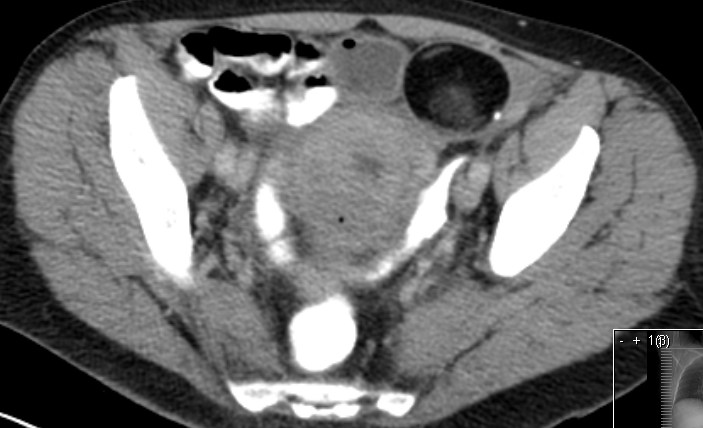

| Fibrom | 62-jährige Frau mit einem Rektumkarzinom und einer

Raumforderung des linken Ovars. ![]() |

Makroskopie: 6,5 x 6 x 4 cm großes Ovar. Es enthält einen 6 cm durchmessenden Knoten.

Dieser mit weißlichen, derben Schnittflächen. Der Knoten ist glatt begrenzt.![]() |